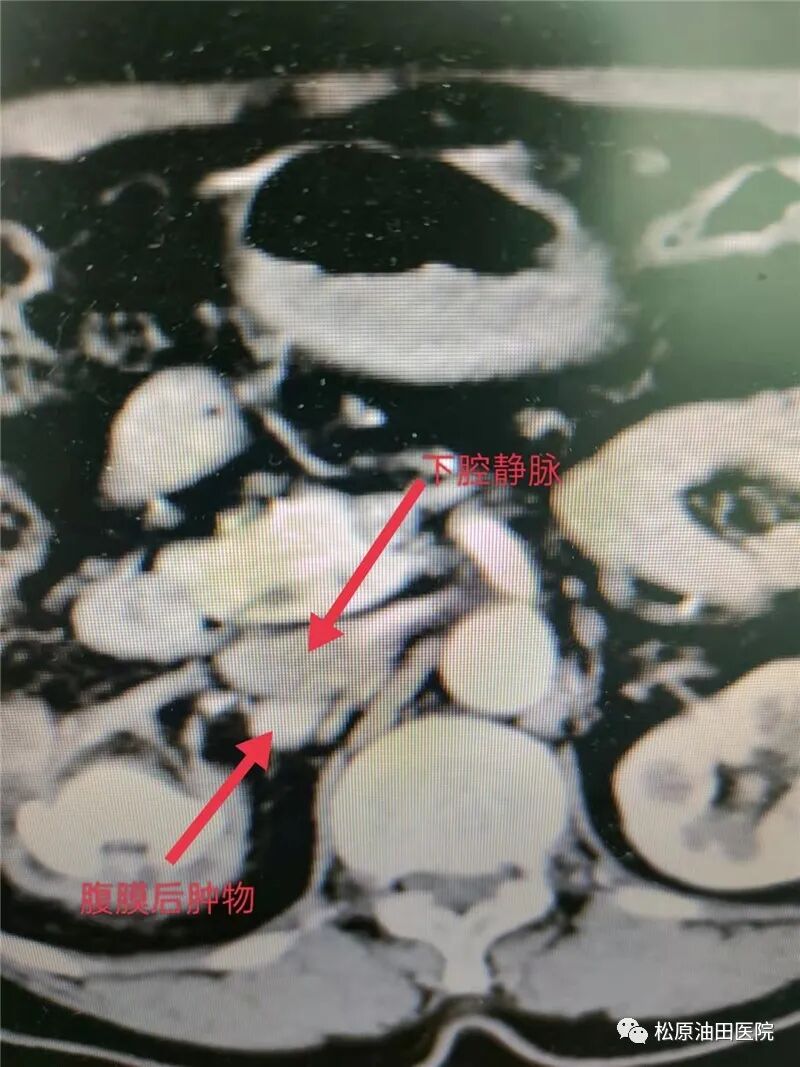

患者知道自己右肾结石多年,期间未予重视,近一时期反复性出现了右腰腹部不适。于是,他近日来到松原吉林油田医院泌尿外科进行诊疗,在检查中发现患者右肾无功能,同时发现同侧腹膜后肿物,与下腔静脉紧密相连。在接受手术过程中,发现腹膜后肿物位于腔静脉表面,肾动静脉就藏在其后,这样,就给手术带来极大风险。刘树志主任在腹腔镜团队和影像科、麻醉科的默契配合下,凭借以往相似病例的经验和娴熟技术,顺利切除右肾及腹膜后肿物2个,手术再一次获得成功。

刘树志主任介绍说:“腹腔镜下腹膜后肿物切除术是一个手术难度比较高,风险比较大的手术。它难度在哪里呢?主要是腹膜后,特别是右侧有那个毗邻强静脉、肾动脉、肾静脉等,还有静脉复合虫这些血管儿,血运特别丰富。这个肿物发生粘连了,组织密切接触了,在分离过程中,如果一不小心造成血管损伤引起大出血,将会危及患者生命,也可能造成手术的一个失败。所以我们这两年做了4例这样的手术,通过不断地进行经验积累,已经成熟。患者呢创伤非常小,而且恢复的速度非常快,患者满意度非常高。同时也是离不开影像科、麻醉科等兄弟科室的大力帮助和支持。”